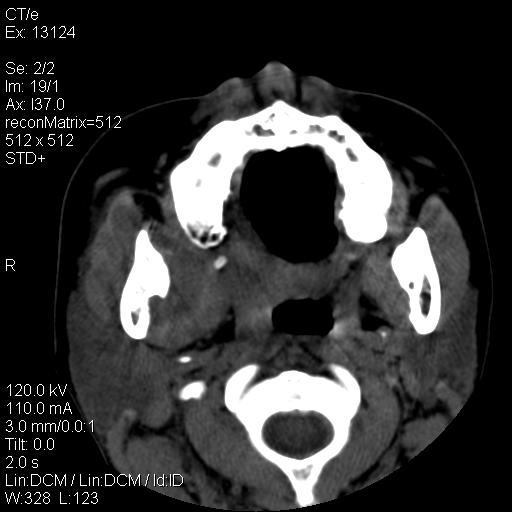

女,29岁,右下磨牙痛,因产后2月,故未治疗。现右颌肿痛伴张口困难。请大家看看右侧鼻咽部、口咽部是否

1.考虑右侧下颌区脓肿(牙源性)

考虑右下智齿冠周炎伴周围软组织炎症,脓肿形成

1)考虑右侧下颌区软组织脓肿(牙源性)。2)鼻咽部炎性改变;建议追踪复查。3)右侧上颌窦炎。4)双侧下鼻甲黏膜肥厚。

1)考虑右侧下颌区牙源性软组织脓肿。2)右侧上颌窦炎。3)双侧下鼻甲黏膜肥厚。4)鼻咽部炎性改变;建议追踪复查。

考虑右下智齿冠周炎伴周围软组织脓肿形成。